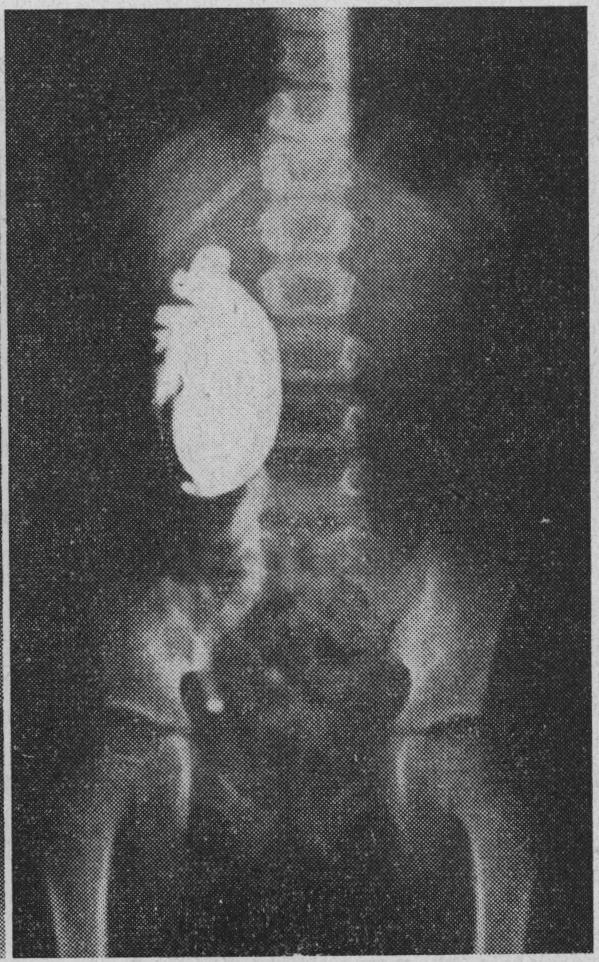

https://cdn.ncbi.nlm.nih.gov/pmc/blobs/89df/1814420/99a3891214de/brmedj02625-0040-a.jpg